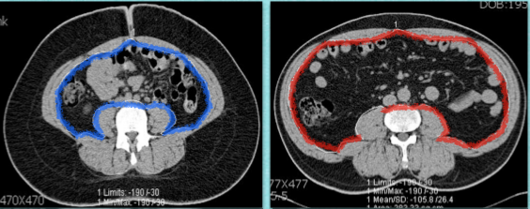

비만, 더 정확하게 말하면 지방은 인슐린 저항성에 직접적인 영향을 미친다. 특히 피하지방보다는 내장지방이 인슐린 저항성을 더 높인다. 그런 이유로 내장지방으로 인한 복부비만은 인슐린 저항성을 추정해 볼 수 있는 지표로 활용되기도 한다. 대사증후군의 주요 진단 요소 중 하나에 복부비만(한국인 기준 남성 90cm, 여성 80cm일 경우)이 포함돼 있는 것도 같은 이유다.

피하지방과 내장지방

▲(왼쪽) 피하지방이 많은 경우, (오른쪽) 내장지방이 많은 경우.